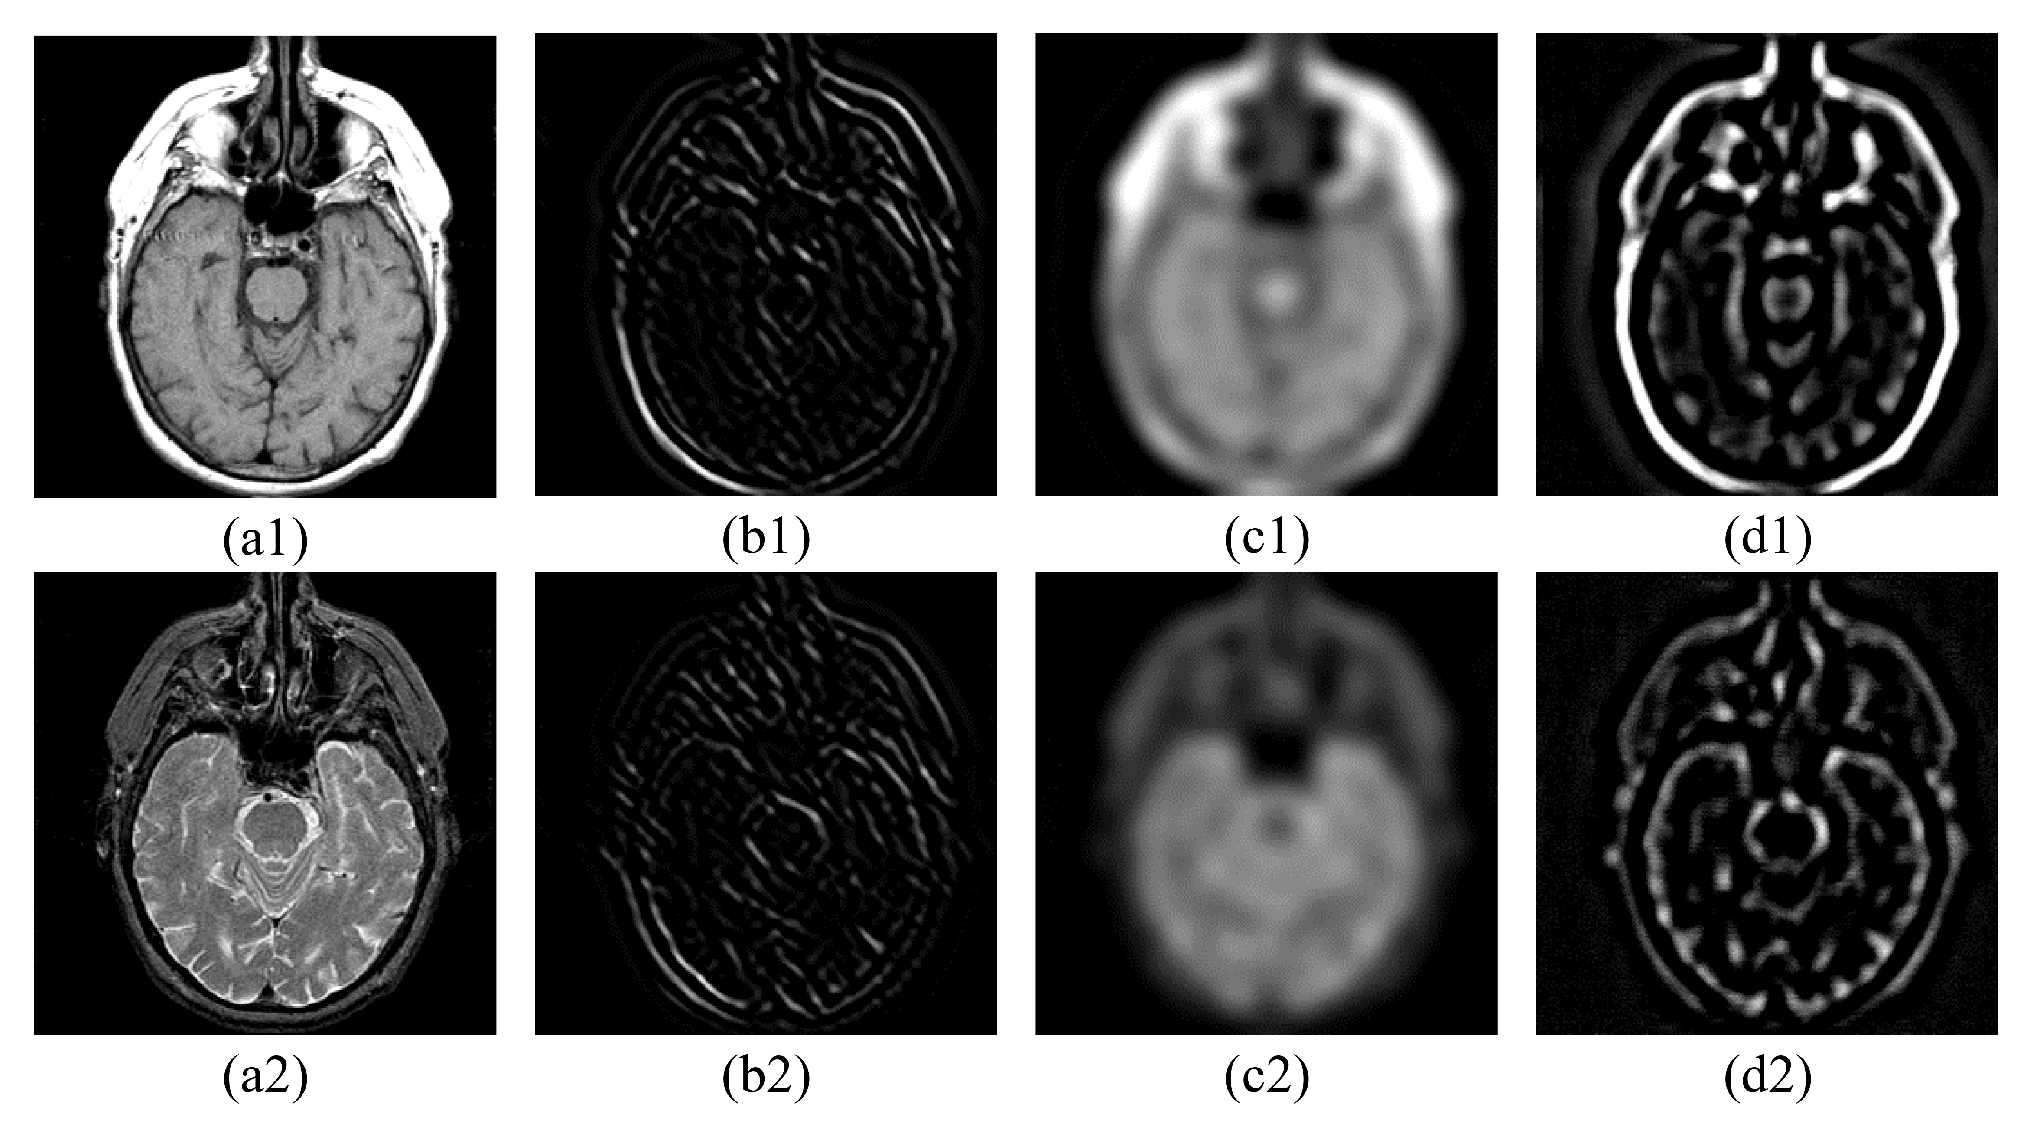

4.1. Nonsubsampled Shearlet Transform (NSST)

5.1.1. Experimental Images

5.2.1. Fusion Analysis on T1-T2